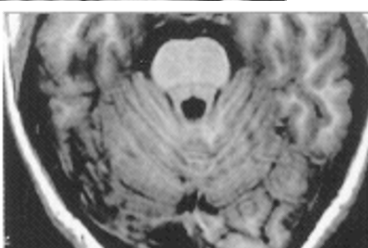

16

Q

which one is T1 and which is T2

A

L: T1

R: T2